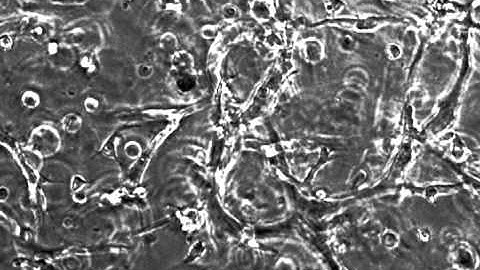

Viscoelastic Finite Element Modeling of Cardiomyocyte Contraction in a Hydrogel-2